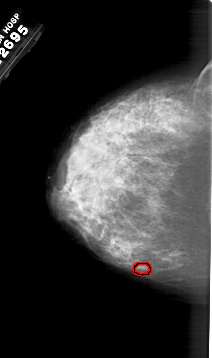

A_1983_1.LEFT_CC

LEFT_CC LINES 6436 PIXELS_PER_LINE 3811 BITS_PER_PIXEL 12 RESOLUTION 43.5 OVERLAY

FILE: A_1983_1.LEFT_CC.OVERLAY

TOTAL_ABNORMALITIES 1

ABNORMALITY 1

LESION_TYPE CALCIFICATION TYPE PUNCTATE DISTRIBUTION CLUSTERED

ASSESSMENT 4

SUBTLETY 1

PATHOLOGY MALIGNANT

TOTAL_OUTLINES 1

BOUNDARY